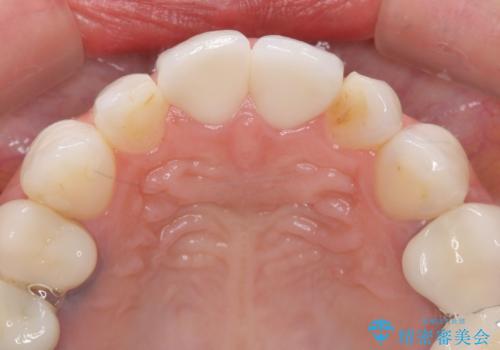

ラミネートベニヤの破折 ジルコニアクラウンによるやり替え

- 欠けてしまった前歯のラミネートベニヤと見た目の改善を求めて来院されました。

歯の大きさの不揃いと、虫歯の再発を認めたためラミネートのやりかえではなく一挙に問題の解決のできるジルコニアクラウンでの治療を計画します。

歯の大きさの不揃いが改善されただけでなく、色調もよくなり審美性をしっかりと改善することができました。